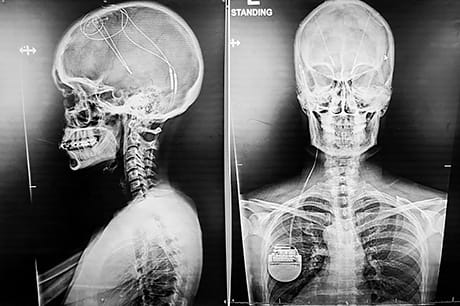

Understanding DBS

Patients who elect to undergo DBS have electrodes implanted in specific areas of their brain. A device for generating electrical signals is also implanted under the skin of the chest and connected to the electrodes in the brain by a thin wire. The electrodes send electrical impulses that help regulate abnormal brain activity.

The DBS procedure involves 3 stages:

- Bone marker implant and imaging – MRI and CT scans done under anesthesia for planning the surgery

- Lead implantation – DBS leads placed precisely in the targeted area of the brain to improve symptoms

- Battery implantation – DBS leads connected to a neurostimulator implanted in the chest

Three weeks later, the device is turned on and fine-tuned to the patient’s needs.